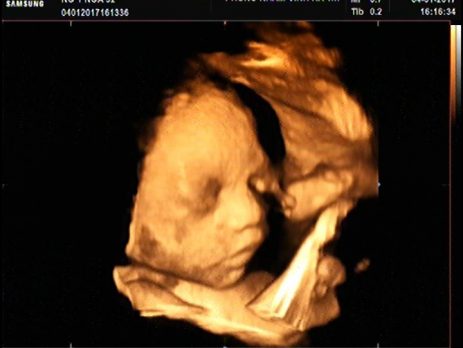

SIÊU ÂM THAI

Khoảng sáng sau gáy (độ mờ da gáy, nuchal traslucency – NT) là 1 đặc điểm hình thể trên siêu âm do sự tích tụ dịch dưới lớp da phía sau cổ thai nhi trong tam cá nguyệt đầu tiên của thai kỳ. Đây là 1 tổ chức có [...]